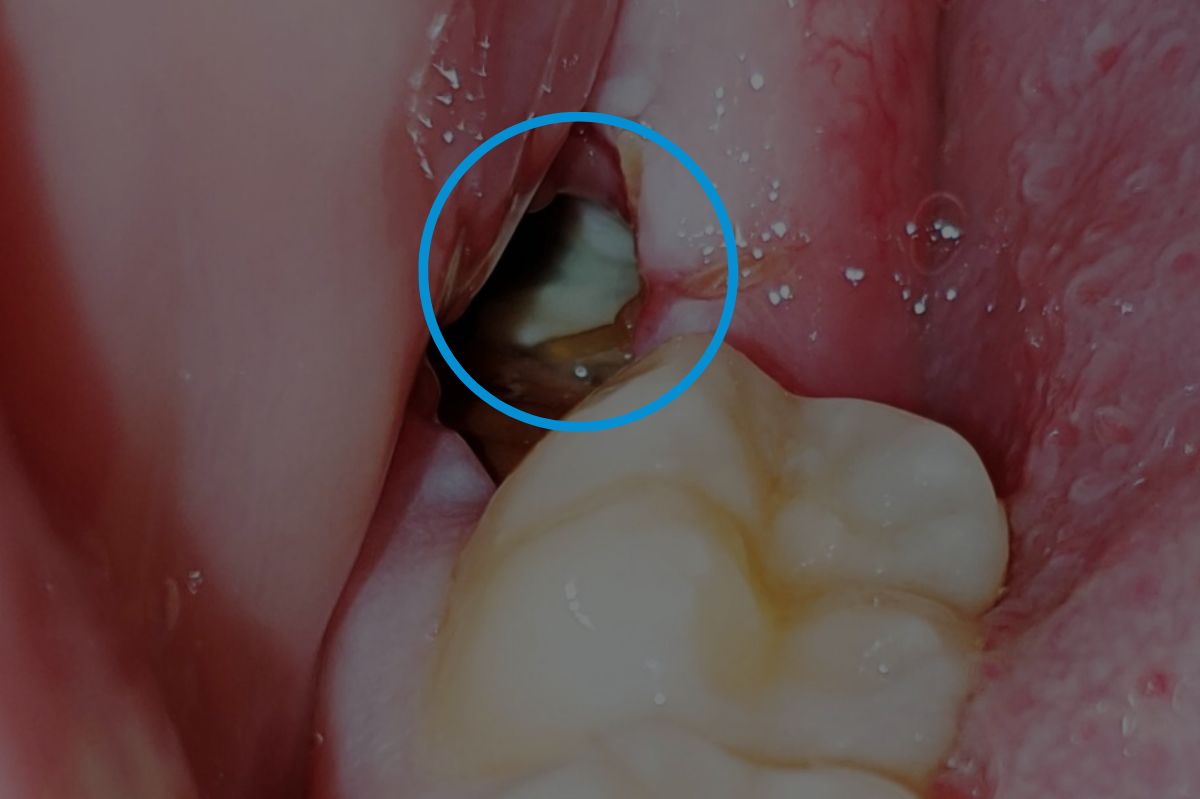

• Dry Sockets: A common issue where the blood clot becomes dislodged, exposing the bone. This leads to a dull ache around the third to fifth day after surgery. Treatment involves medicated dressings for pain relief and may require multiple visits to replace the dressing.